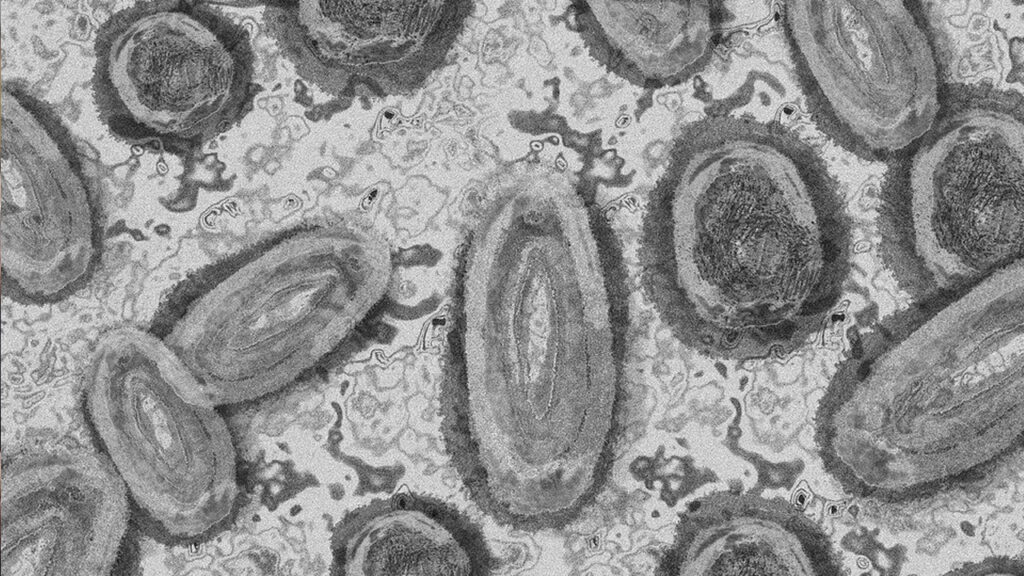

En México aumentaron el número de casos de viruela símica que llegó a los 788, distribuidos en 28 entidades, pues se sumaron Nayarit, Campeche e Hidalgo.

De acuerdo con la Secretaría de Salud, se han identificado mil 678 casos que cumplen con la definición de viruela del mono hasta el 5 septiembre de estos sólo 788 fueron positivos, 596 fueron descartados y 294 se encuentran actualmente en estudio.

El 98% de los casos confirmados son en hombres, mientras que el grupo erario de 30 a 39 años es el mayormente afectado con 350 de los 788 contagios.